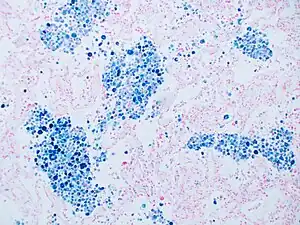

Stain for iron

Prussian blue is a common histopathology stain used by pathologists to detect the presence of iron in biopsy specimens, such as in bone marrow samples. The original stain formula, known historically (1867) as "Perls Prussian blue" after its inventor, German pathologist Max Perls (1843–1881), used separate solutions of potassium ferrocyanide and acid to stain tissue (these are now used combined, just before staining). Iron deposits in tissue then form the purple Prussian blue dye in place, and are visualized as blue or purple deposits.[39]

Histopathology of the liver, showing a Kupffer cells with significant hemosiderin deposition next to a hepatocyte with lipofuscin pigment. H&E stain.

Histopathology of the liver, showing a Kupffer cells with significant hemosiderin deposition next to a hepatocyte with lipofuscin pigment. H&E stain. Prussian blue staining, highlighting the hemosiderin pigment as blue.

Prussian blue staining, highlighting the hemosiderin pigment as blue. Prussian blue stain

Prussian blue stain